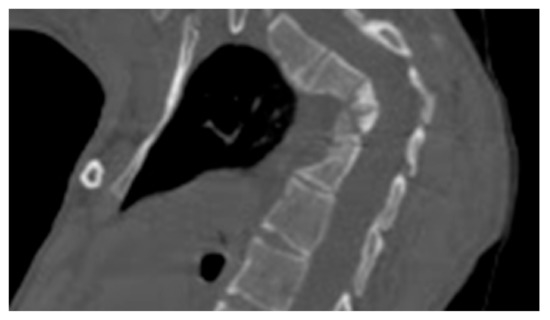

- 3D reconstruction CT scan in a-20-years-old-girl showed severe flattening, fusion, shrinkage and compression of the vanished thoracic spine T3-T9 causing effectively the development of painful kyphoscoliosis. Vanishing bone extended to involve the right shoulder joint resulted in total drop of the right upper limb (Figure 3).